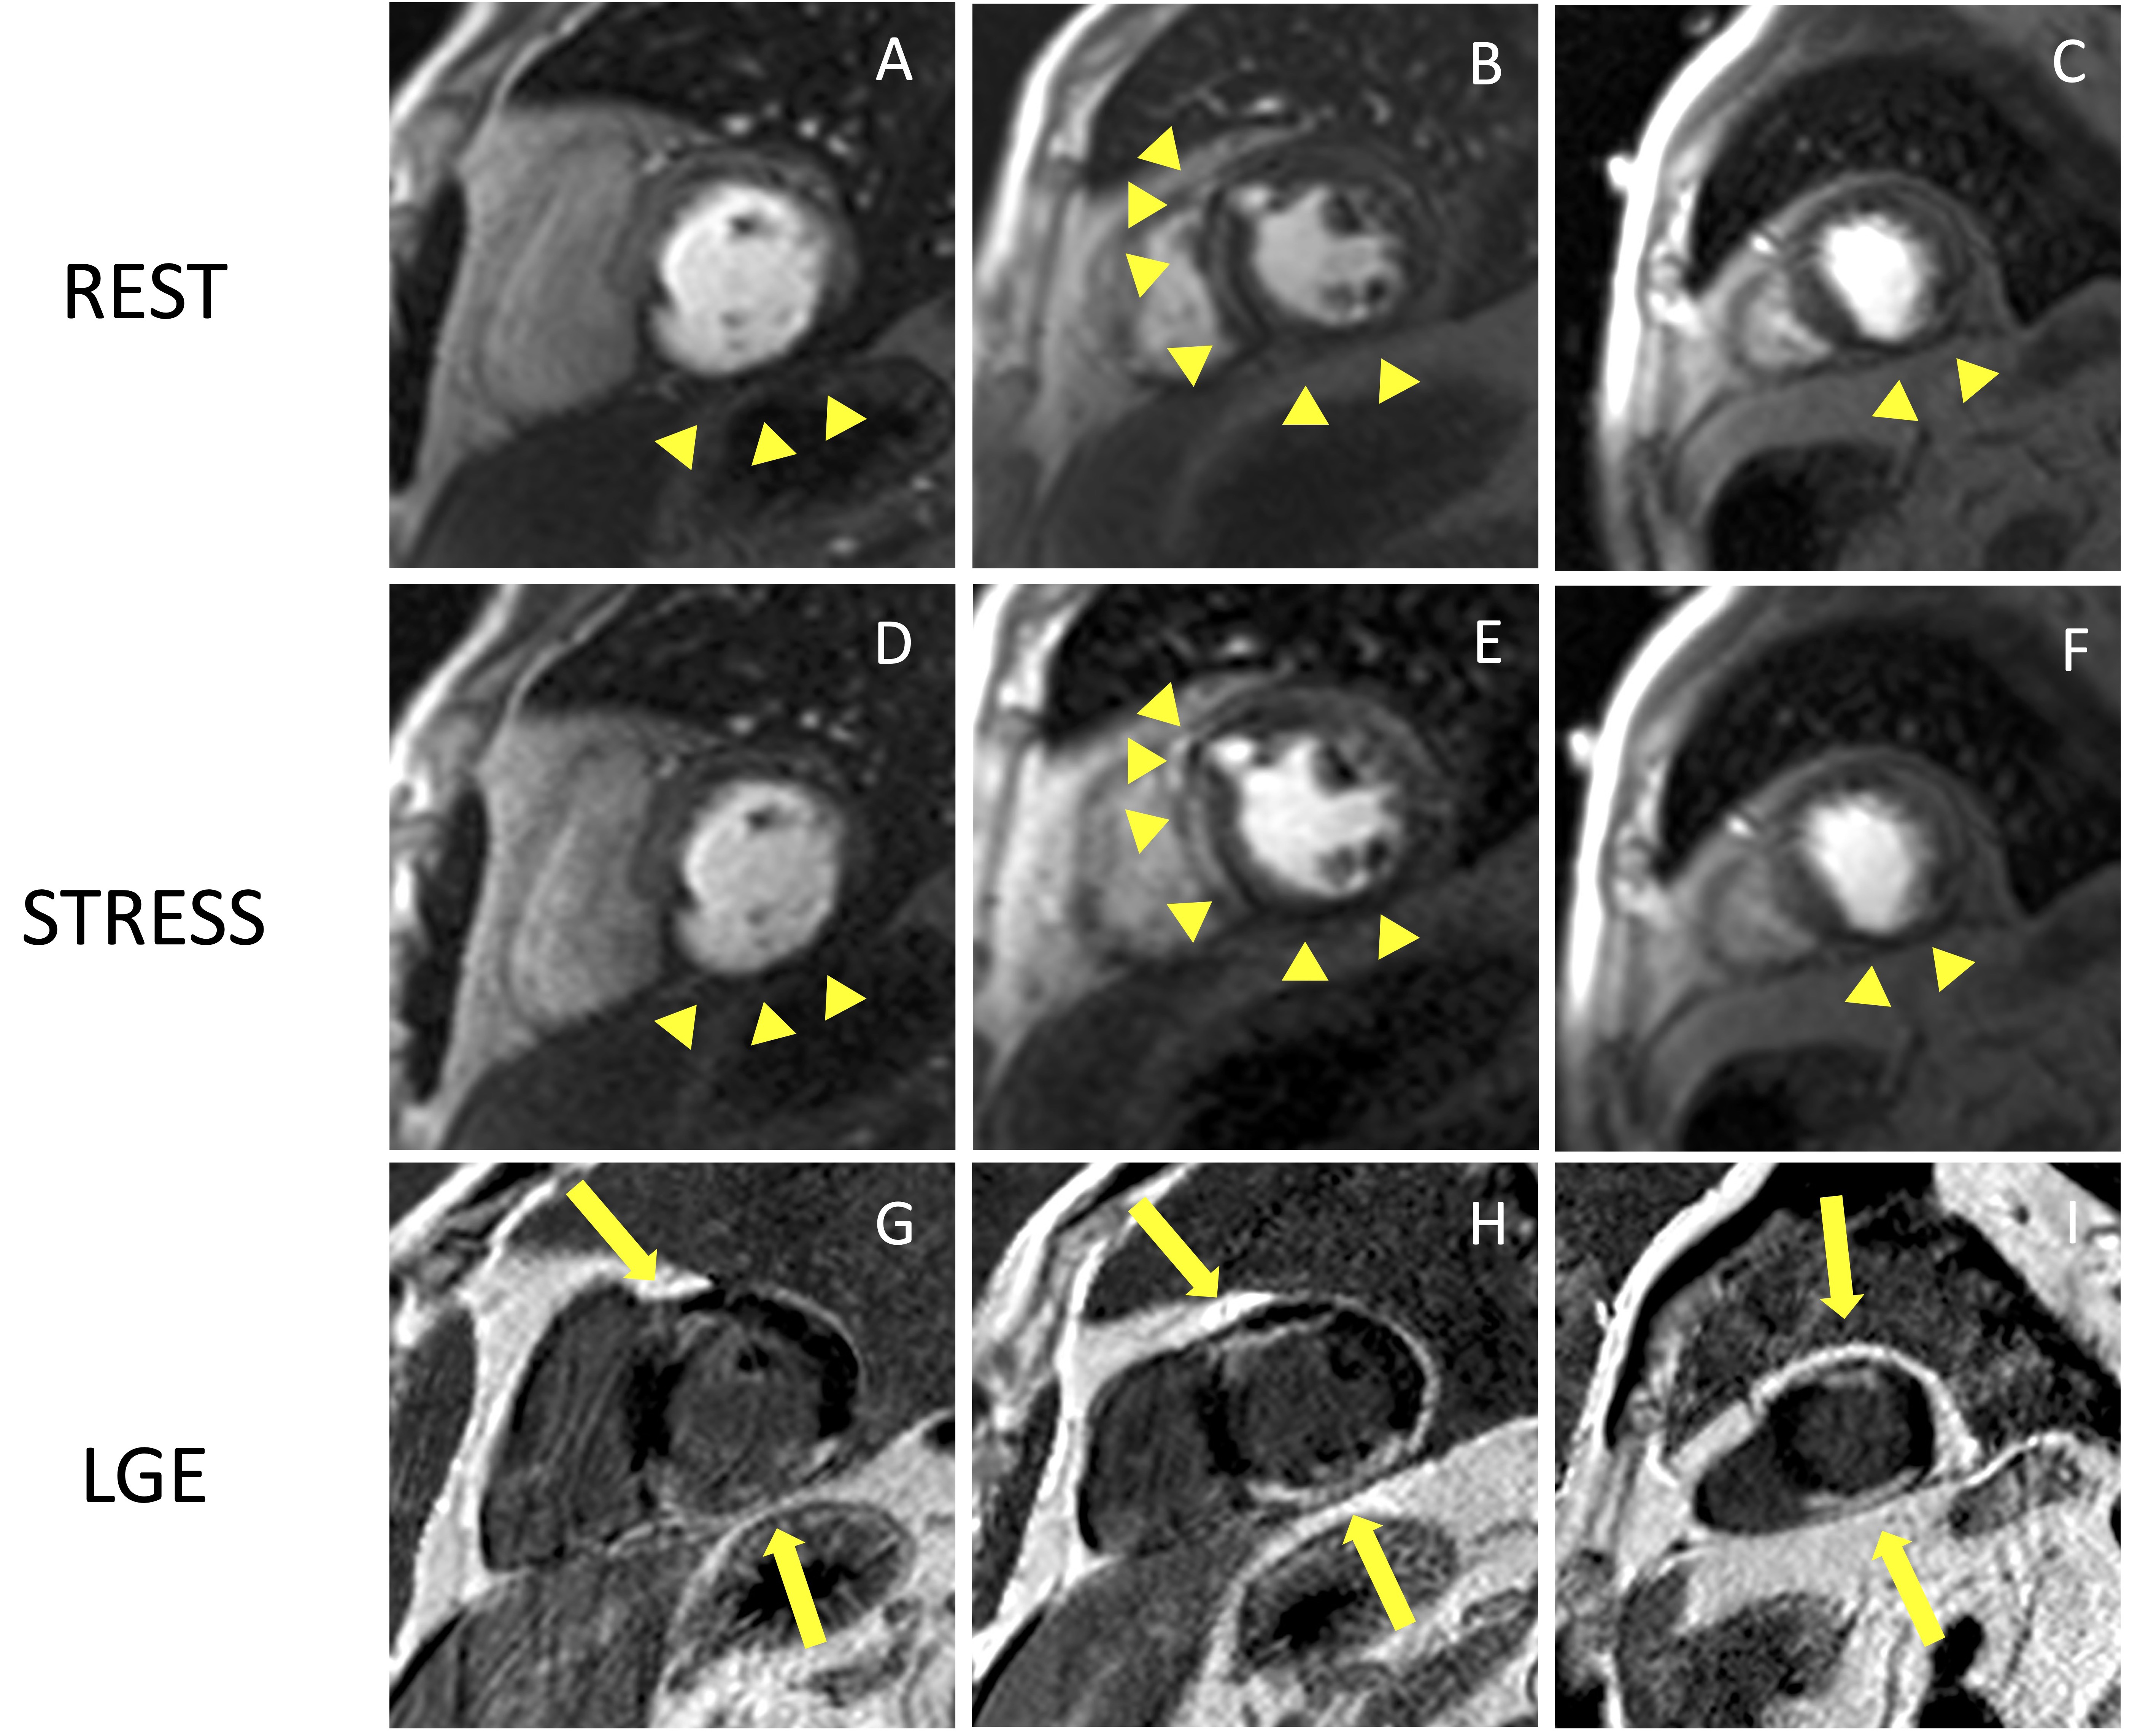

The perfusion images are analyzed using the American Heart Association (AHA) 16-segment model [29]. By assessing the number of segments with perfusion defects due to ischemia, the global ischemic burden can be estimated. The perfusion defect is usually most evident about three heart beats after the maximal contrast enhancement of the ventricular cavity and continues while the contrast washes out. It is important to distinguish inducible perfusion defects from artifacts. The most common is the ‘dark-rim artifact’, which appears as a hypointense area in the subendocardial layer of the myocardium, usually due to low spatial and temporal resolution (Fig. 3). Dark rim artifacts usually appear as the gadolinium first reaches the ventricular cavity, but it vanishes once the myocardium is enhanced. Moreover, they are present during both rest and stress conditions in the absence of underlying scars in the LGE images.

Fig. 3.Example of stress CMR images showing the ‘dark-rim artifact’. CMR adenosine-stress perfusion in a 44-year-old man with a known congenital coronary artery abnormality (RCA with a high take off and inter-arterial course). Short axis rest and stress perfusion images are shown respectively at the basal (A,D), mid-ventricular (B,E), and apical (C,F) levels. There is evidence of a transient hypointense area in the subendocardial layer of the mid-ventricular septal segments (yellow arrows) both in the rest and stress images (B,E), during the early phase of passage of GBCA bolus through the left ventricle, suggestive for “dark rim artifact”. Corresponding LGE images (G,H,I) show no myocardial scars. CMR, cardiovascular magnetic resonance; LGE, late gadolinium enhancement; RCA, right coronary artery; GBCA, gadolinium-based contrast agent.